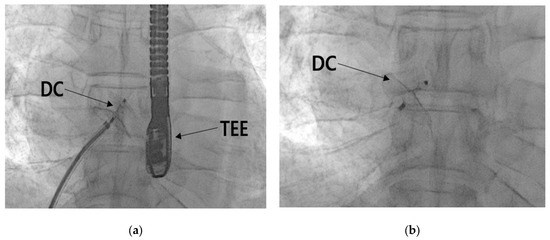

2.2.4. Patent Foramen Ovale Closure

3. Discussion